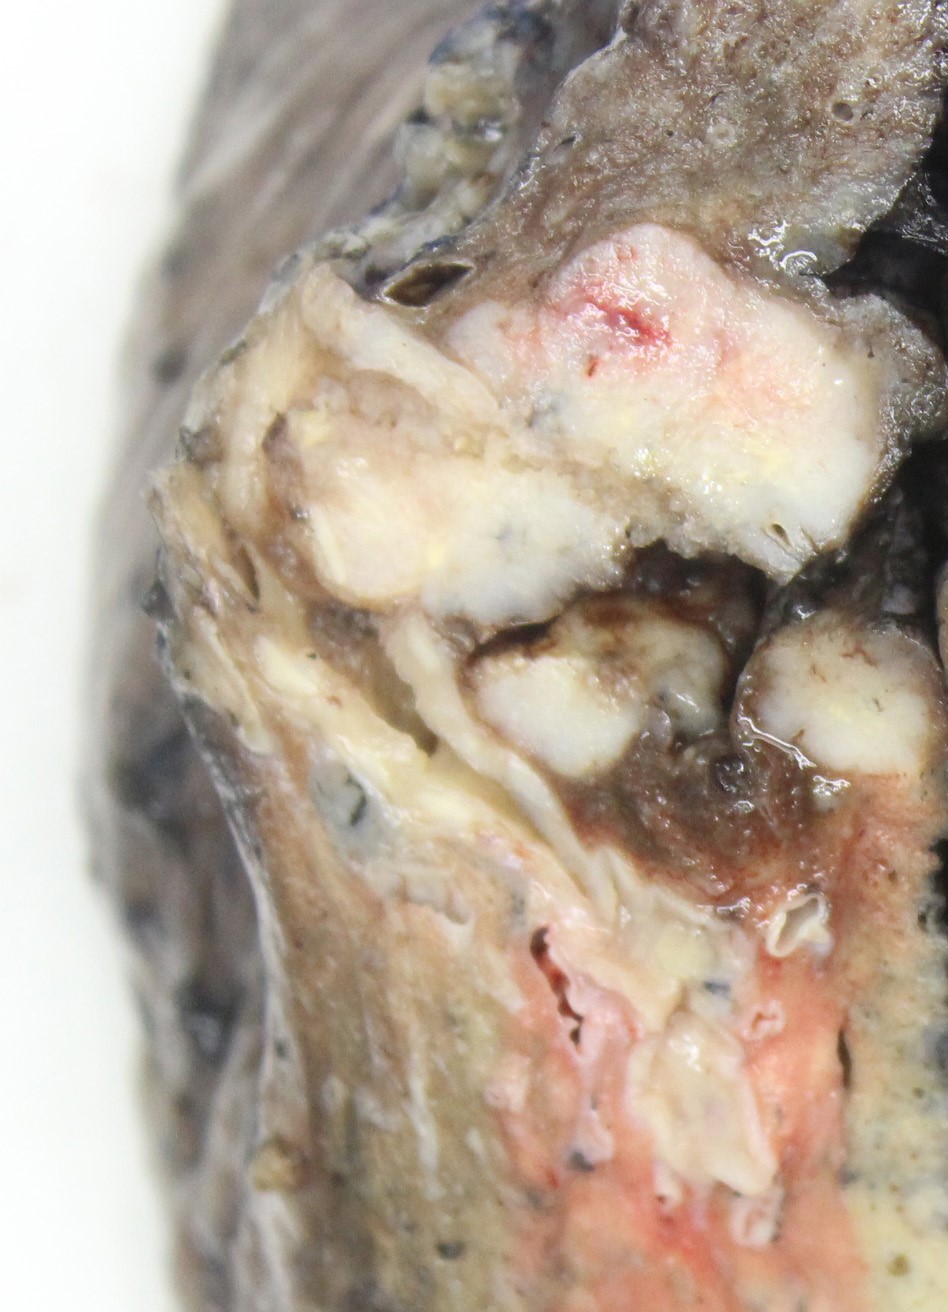

Gross description

- Gross appearance is indistinguishable from other lung malignancies

- Most tumors tumors are located peripherally and are usually nodular and circumscribed with tan-red, necrotic cut surface (Am J Clin Pathol 2004;122:884, AJR Am J Roentgenol 2004;182:87)

- Size range: 0.9 - 12 cm, with average size 3 - 4 cm (Cancer 2001;91:1992)